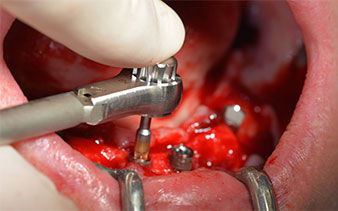

The mental foramen was first identified as a limiting anatomical structure and then the cortical bone of the crest was smoothed with the straight handpiece and a large rose-head bur (Fig. 4).

This is where the first advantages of Implantmed become obvious. The surgical protocol is already preset and the settings stored at fixed positions. The individual positions can be selected by simply pressing the “P” position on the foot control or via the display itself. The preset speed of 35,000 rpm in position 1 in this case is also shown in large figures on the illuminated display (Fig. 5 and 6).

The surgical protocol for the implants employed (SKY, bredent medical) specifies a speed of 1,200 rpm for the pilot drilling (Fig. 7 - 9).

This corresponds to the next preset position in the Implantmed. Here we see the W&H contra-angle handpiece being held at a 45° angle to mesiocaudal in the region of 45 in order to preserve the mental nerve. The mental foramen is used as the anatomic reference for all drilling in this region. The subsequent holes were drilled at a reduced speed of 300 rpm (Fig. 10 and 11).